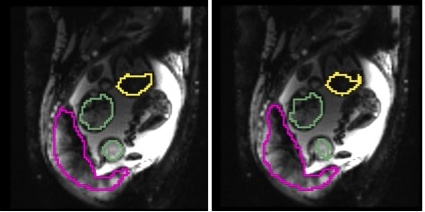

Fig. 2 illustrates results for two example cases from the study. We observe that the reference frame was warped accurately by the algorithm to represent a frame in the series that is substantially different in the regions of the placenta and the fetal liver. The delineations achieved by transferring manual segmentations from the reference frame to the coordinate system of the current frame ( in the figure) are in good alignment with the manual segmentations for the current frame. Fig. 3 reports volume overlap statistics for the placentae, fetal brains, and fetal livers, for each case in the study. We observe that temporal alignment improves volume overlap in important ROIs and offers consistent improvement for all cases over pairwise registration to the reference frame. We also note that temporal alignment offers particularly substantial gains in cases with a lot of motion, i.e., low original volume overlap.